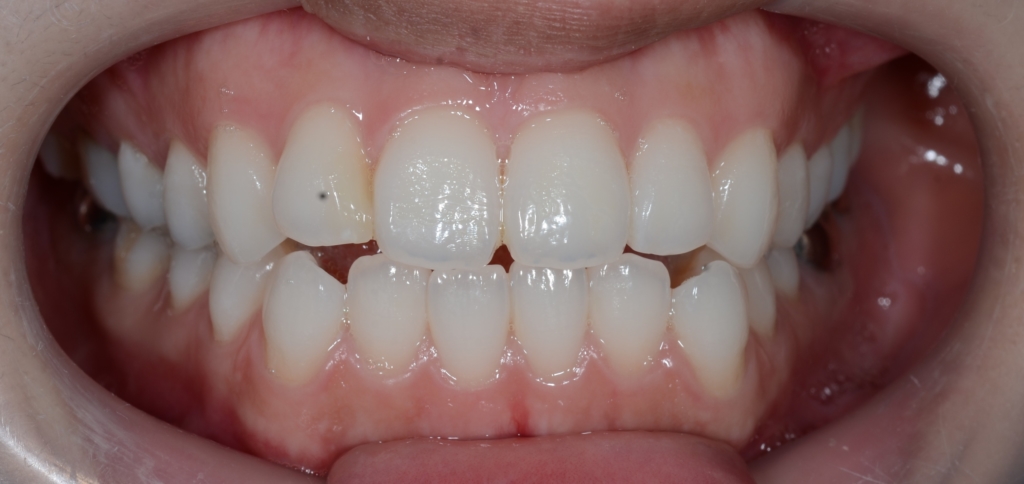

患者さんは、20代の女性(社会人)です。

「口元をいっぱい引っ込めて、口ゴボを治したい!」

というのが主訴です。

【診断】

#1.上下顎前突

#2.open bite (開口)傾向

#3.ガミースマイル

と診断しました。